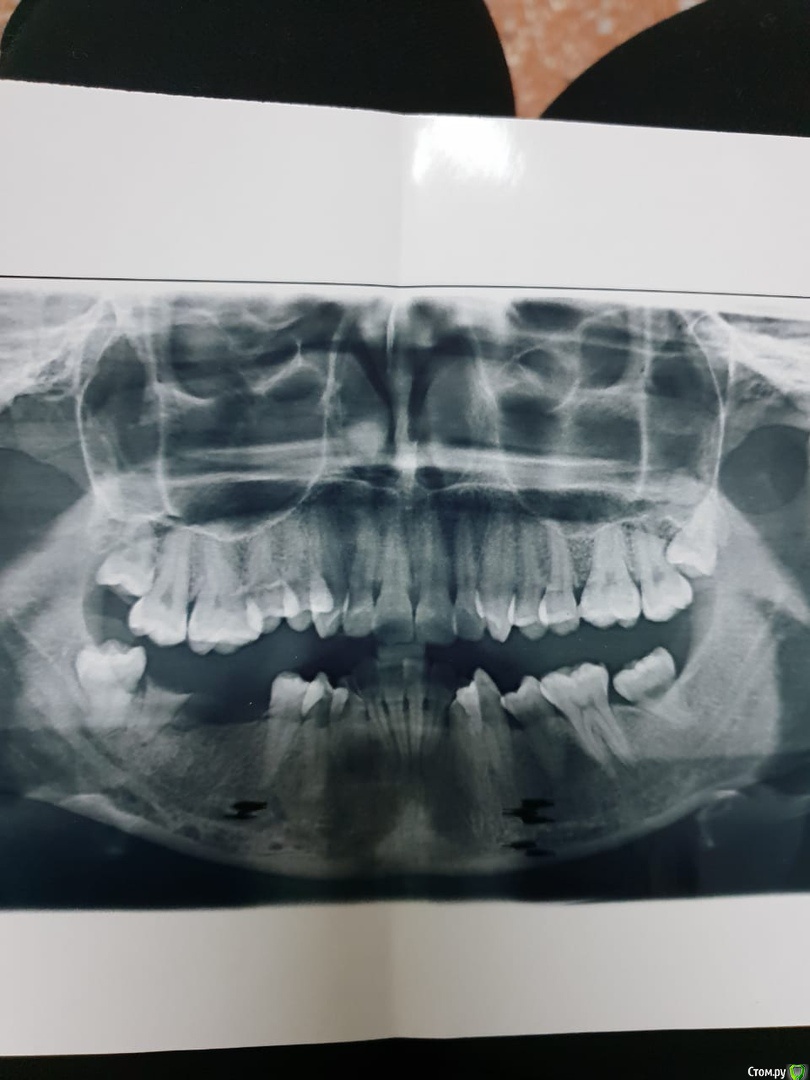

ArtDenis Опубликовано 29 июля, 2019 Поделиться Опубликовано 29 июля, 2019 (изменено) Добрый день. Заранее спасибо за Ваши ответы. Пациентка: Девушка, 30 лет, готовимся к первой беременности, поэтому занялись зубами. Снизу в челюсти долгое время отсутствовали зубы, по этой причине верхние зубы опустились вниз.Нижний 7-ой корень и 8-ку мы уже удалили. Ходили к нескольким ортодонтам и у них расходятся мнения по подъему опустившихся зубов.1) Чтобы поднять зубы, нужно удалить верхнюю возьмерку, а затем с помощью мини-импланта (какие-то небольшие шурупы) поднимать зубы.2) Восьмерку сверху удалять не нужно, так как за нее можно будет зацепиться и с помощью упора поднимать зубы мудрости. Эта восьмерка, кстати, вообще не открыта. Какой из вариантов более правильный, как Вы считаете?СпасибоPS: Так как все это затягивается, мы скорее всего сначала все-таки забеременеем, а потом уже будем спокойно заниматься зубами. Могут ли еще сильнее опуститься нижние зубы?Так как верхние восьмерки полностью закрыты и не беспокоят, какова вероятность того, что с ними будут проблемы во время беременности? Изменено 29 июля, 2019 пользователем ArtDenis Ссылка на комментарий